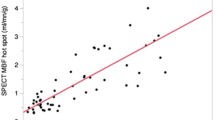

Of the semi-quantitative approaches, one of the most common ones is measuring the upslope of the signal intensity curve in the myocardium (Fig. 13.6). Because only the upslope is measured, this method is dependent wholly on the contrast wash-in and is insensitive to contrast wash-out. During the wash-in, changes in tissue relaxivity are due principally to incoming contrast agent from arterial blood, and the rate of incoming contrast will be proportional to blood flow. However, most contrast agents used in CMR are not intravascular and will leak into the extravascular space, and additionally there is significant spin exchange between intravascular and extravascular compartments. Both of these effects complicate interpretation of relaxivity changes during the wash-out period. By using only the wash-in period, upslope measurement largely avoids these concerns. Because upslope measurement does not give units of flow, it is not an absolute quantitative approach. However, upslope of the AIF is often used to normalize between scans, and a recent publication [42] has suggested that calibrating global upslope (measured across the entire LV) to global flow (measured at the coronary sinus) may allow for absolute quantification.

Peak upslope or area under the curve are often used as semi-quantitative ways to measure perfusion (Reproduced from Lee and Johnson [39], with permission of Elsevier)